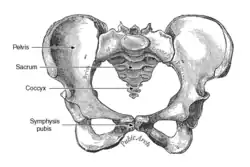

- Sínfise púbica (entre os púbis no osso da cintura pélvica);

- Sínfise sacrococcígea (entre o sacro e o cóccix);